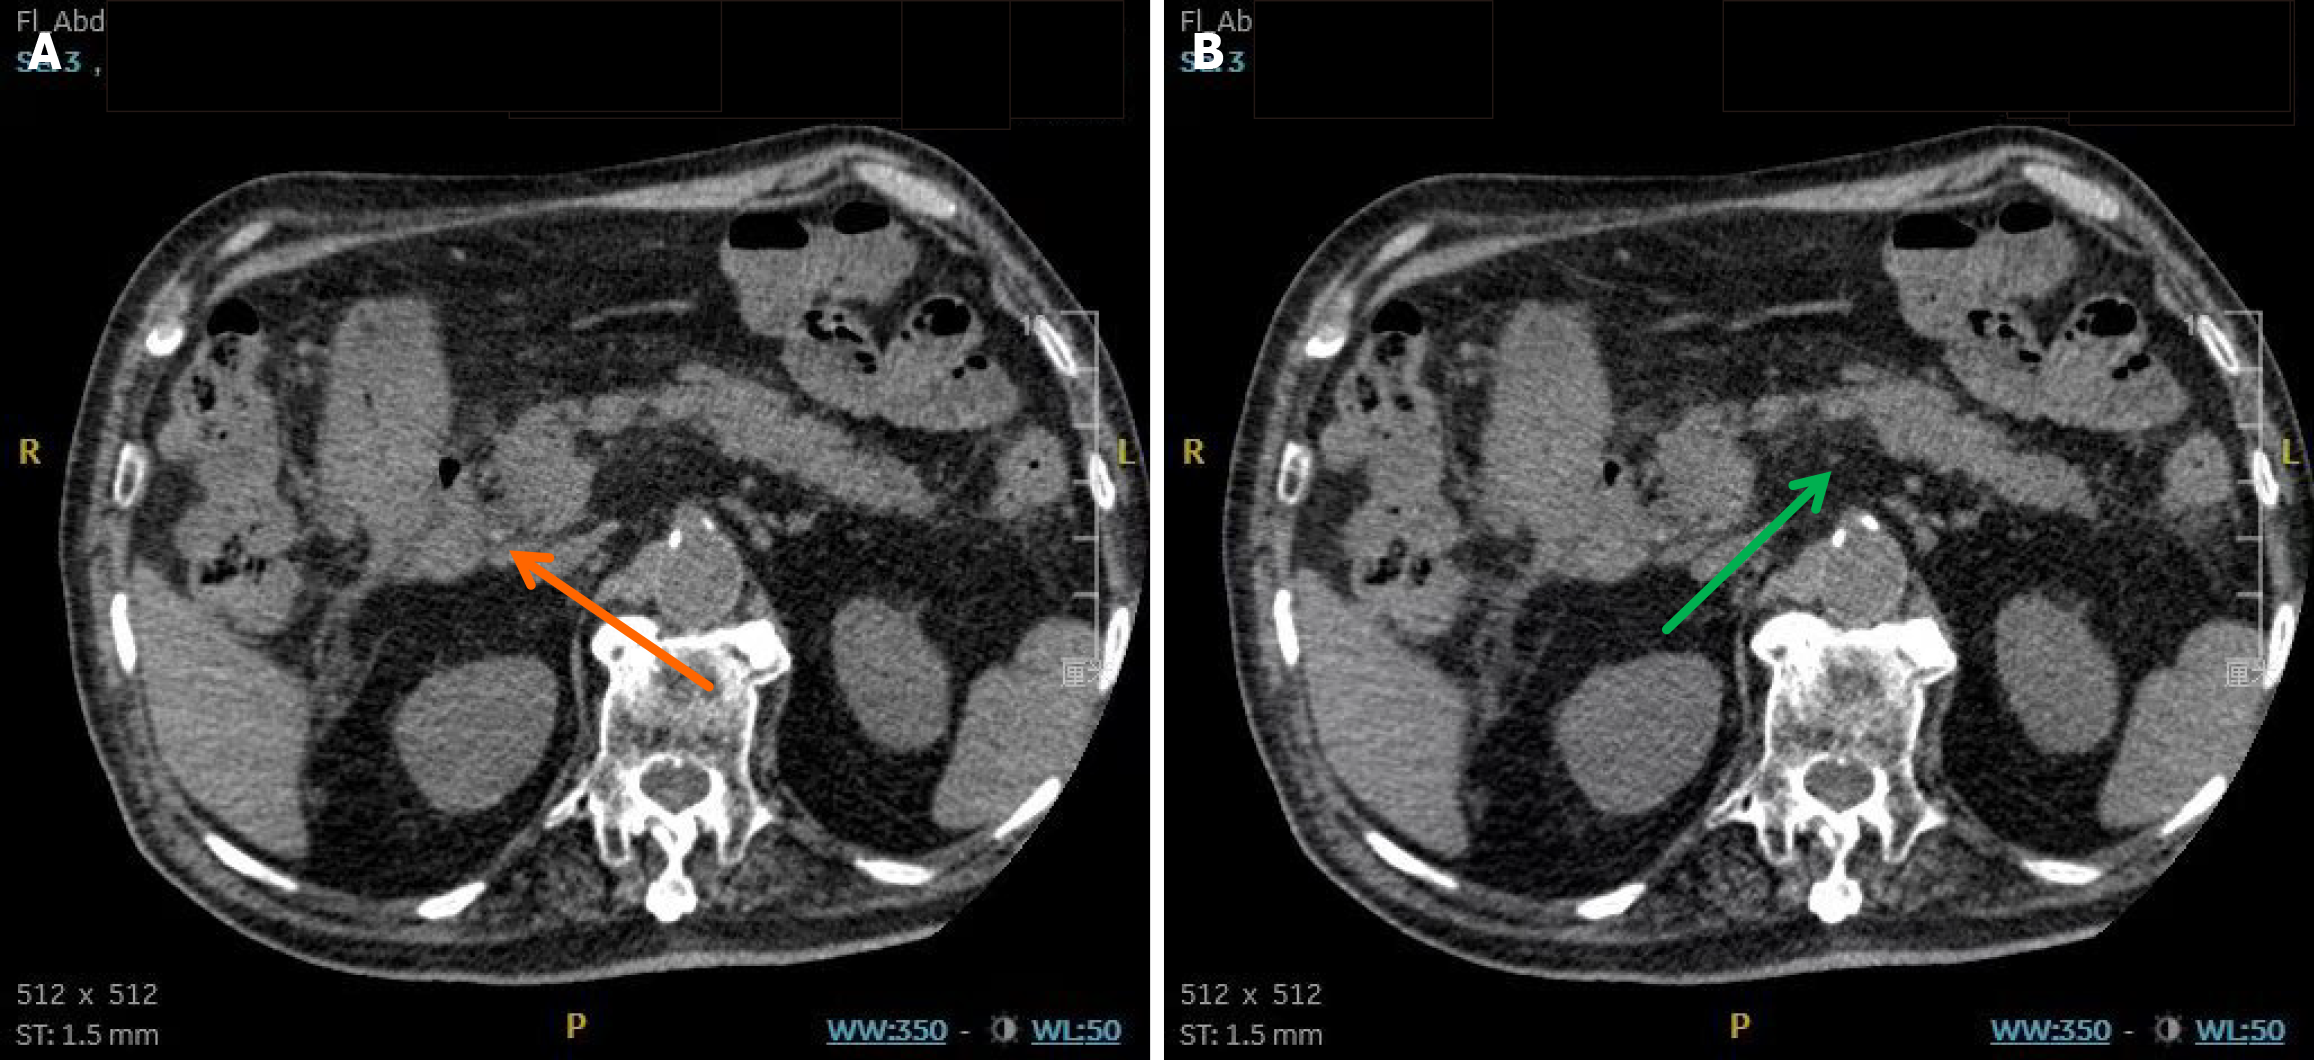

Figure 2 Endoscopic retrograde cholangiopancreatography with endoscopic sphincterotomy, stone extraction, and endoscopic retrograde biliary drainage performed on July 1, 2024.

A: Cholangiography shows dilation of the distal common bile duct (maximal diameter: 1.5 cm) (orange arrow) with an unclear stone shadow; B: The cholangiography showed no residual stones; C: One 5 Fr × 5 cm plastic stent was placed in the common bile duct.